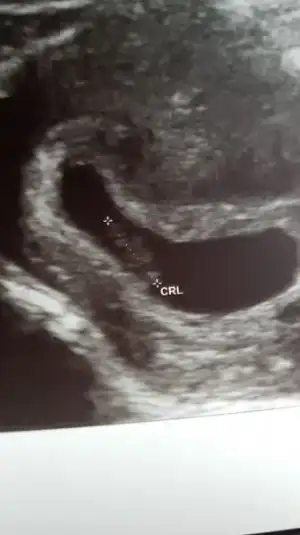

Selam kızlar bende bugün doktora gittim önden gidiyoruz 8+5 deyim. Benim akıntılarım vardı. Son 2 günde kaşıntı olunca doktorum onuda kontrol etti :( mantar... neyse bebek gayet iyiymiş, hareketli de kendisi. Kollar bacaklar çıkmış :) teyzesi bir cinsiyet yorumu da biz alalım. Mantar için bakılınca ultrasonumda vajinal oldu. interiorarchitect interiorarchitect

Maşallah maşallah kuzuya nasıl belirginleşmiş vücudu kafası :) demekki 8. hafta da netleşiyor, ultrason görüntüsü de çok güzel. Allah esirgesin sağlıkla doğsun inşallah canım :)

Maşallah acaba ultrason vajinal oldugu icin mi boyle net? Benim 7+2de karindan ultrasonum var.bebeim o kadar silikki..:110:

Canım daha hiç karından ultrasonum yok benim o yüzden pek bilemiyorum ama 6+5 te benimde öyle onuda yükledim. 2 haftada çok değişmiş.